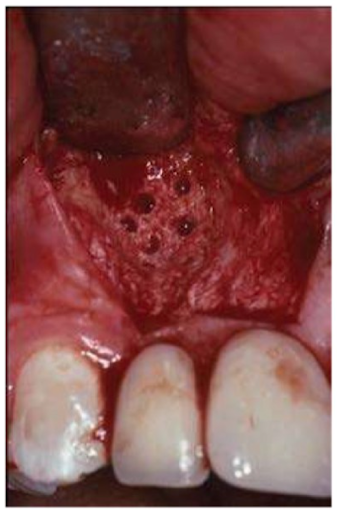

Những mảnh xương nhỏ đã được đặt dưới màng PTFE để duy trì thể tích của vùng ghép. Xương vỏ bên dưới được đục lỗ với mũi khoan phẫu thuật tròn nhỏ để khuyến khích sự xâm nhập của tế bào xương từ xương xốp bên dưới. Tên viết tắt: PTFE – polytetrafluoroethylene.

Xương vỏ bên dưới nên được đục lỗ với mũi khoan phẫu thuật để thúc đẩy các tế bào tạo xương chiếm không gian đã tạo ra.

Đục thủng vùng ghép xương với mũi khoan phẫu thuật cho phép tăng sinh các tế bào xương và mạch máu dưới màng và giữa vùng nhận và vật liệu ghép xương.